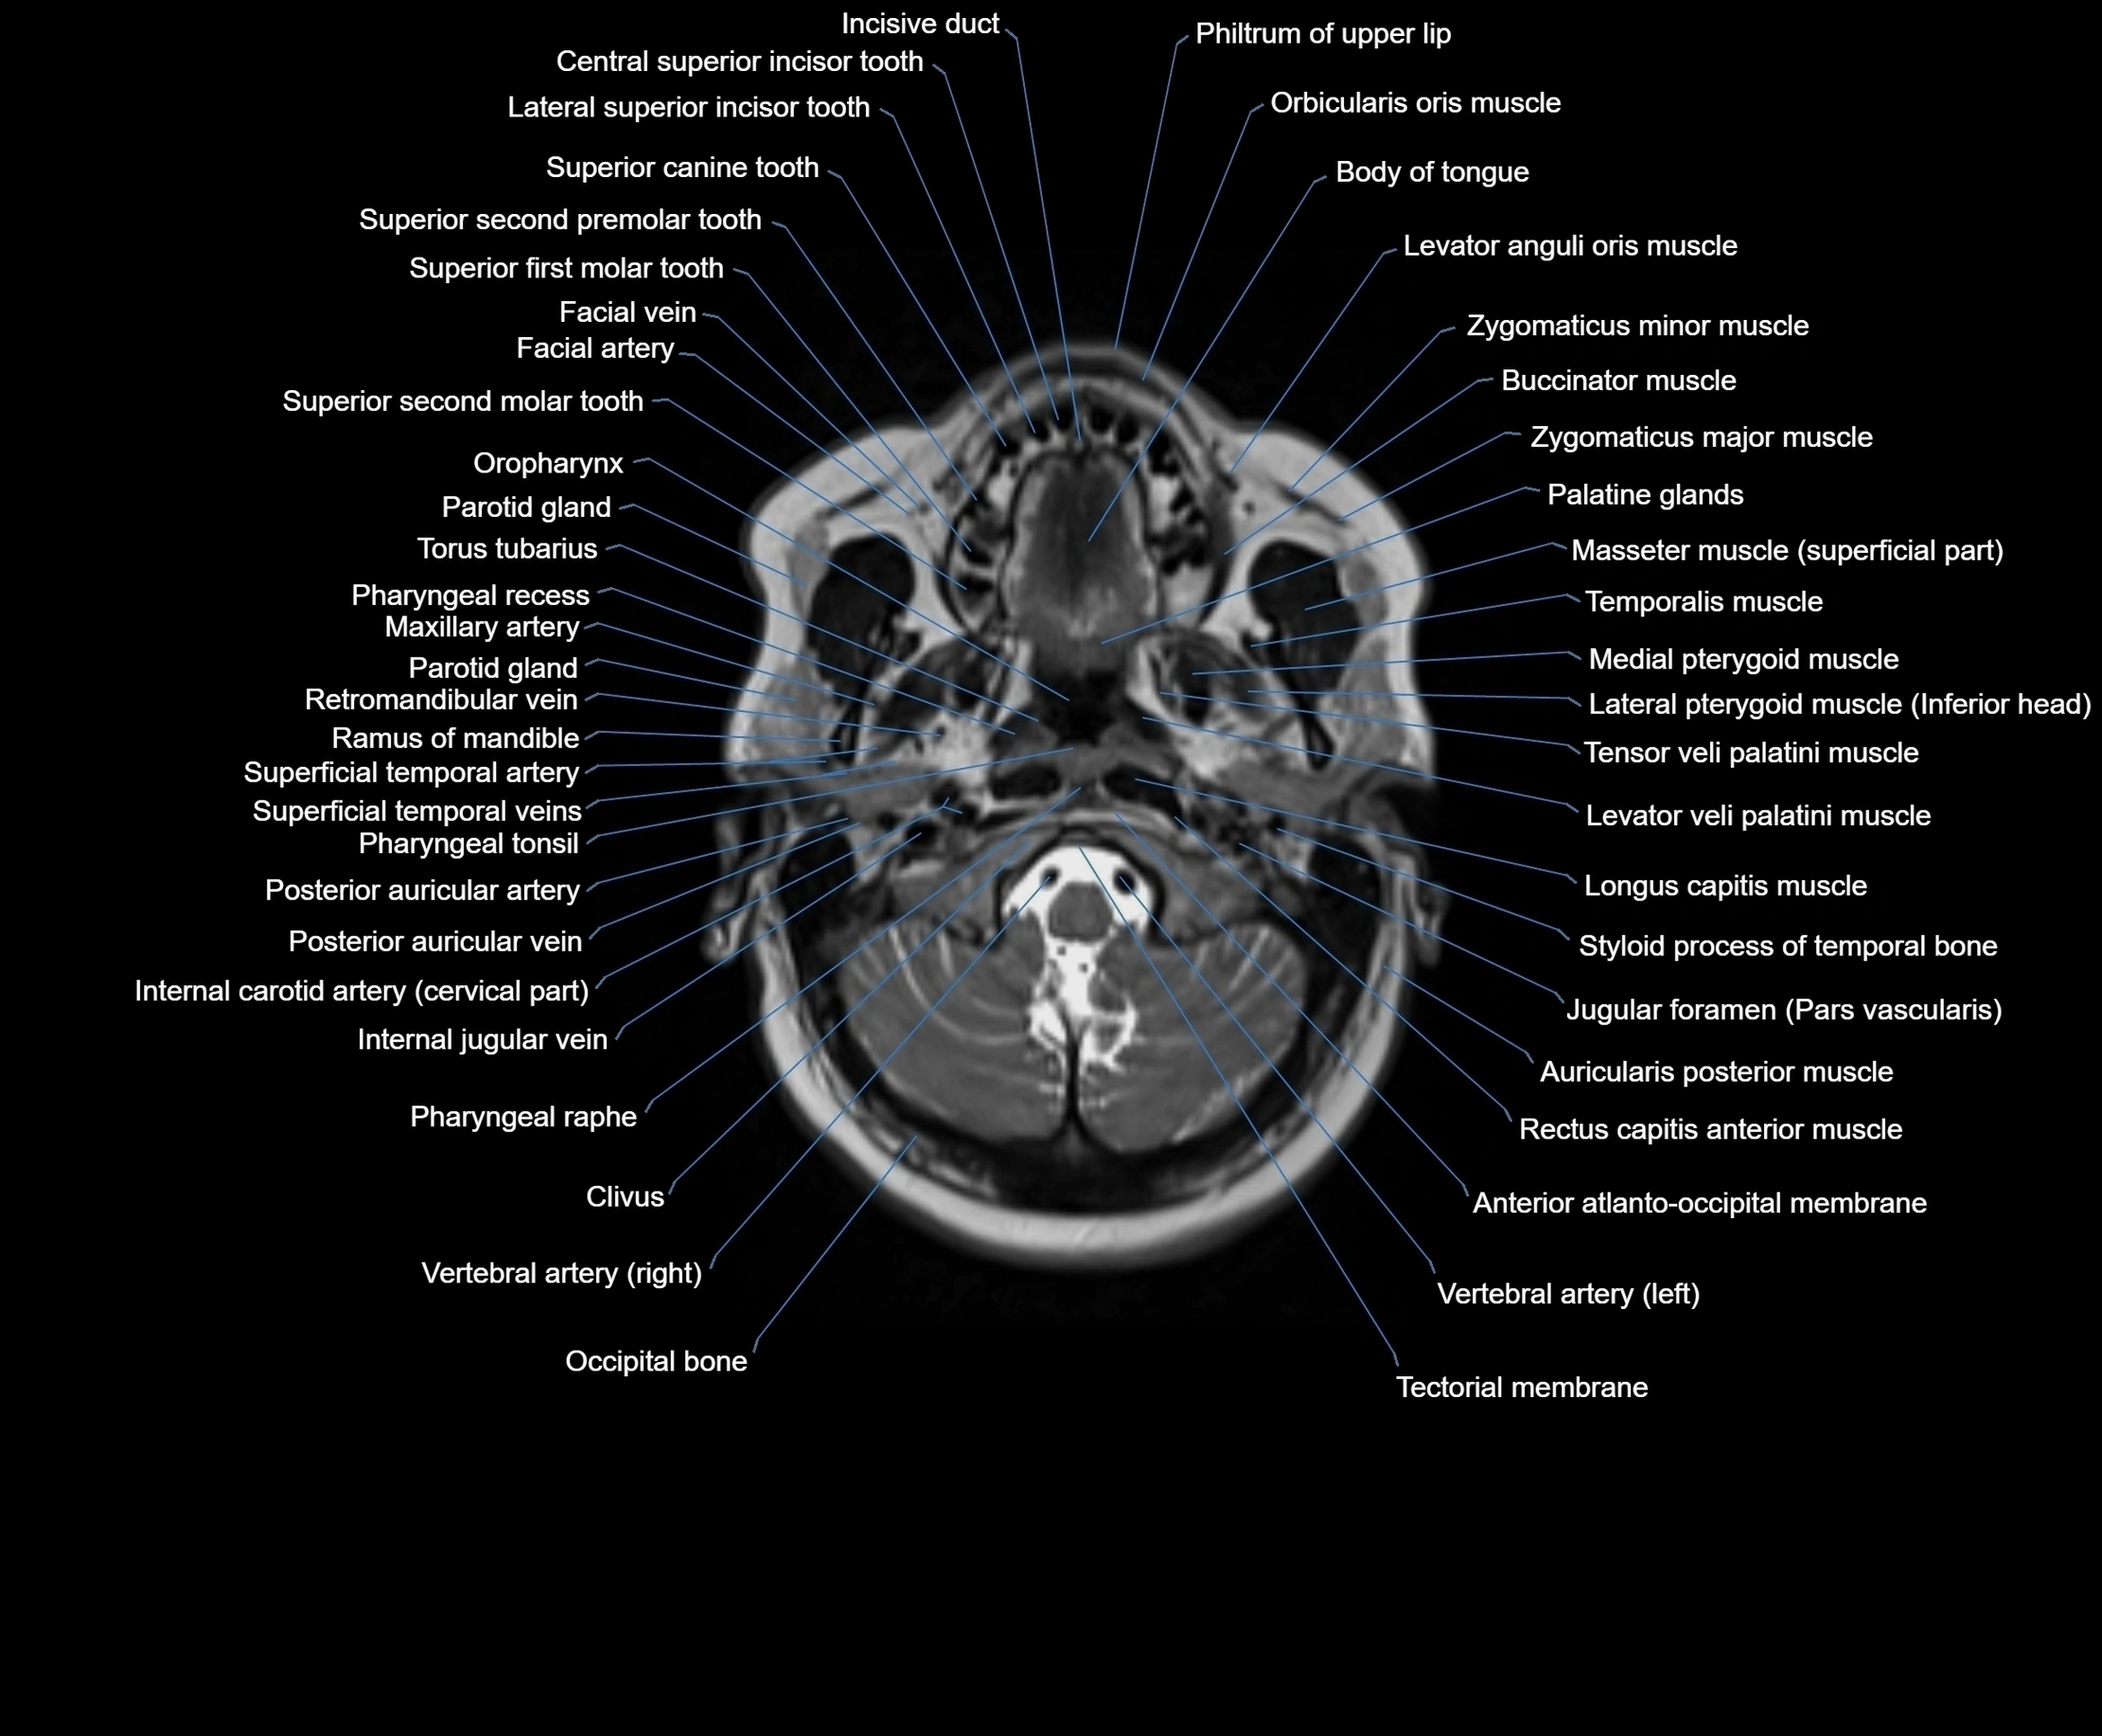

MRI images